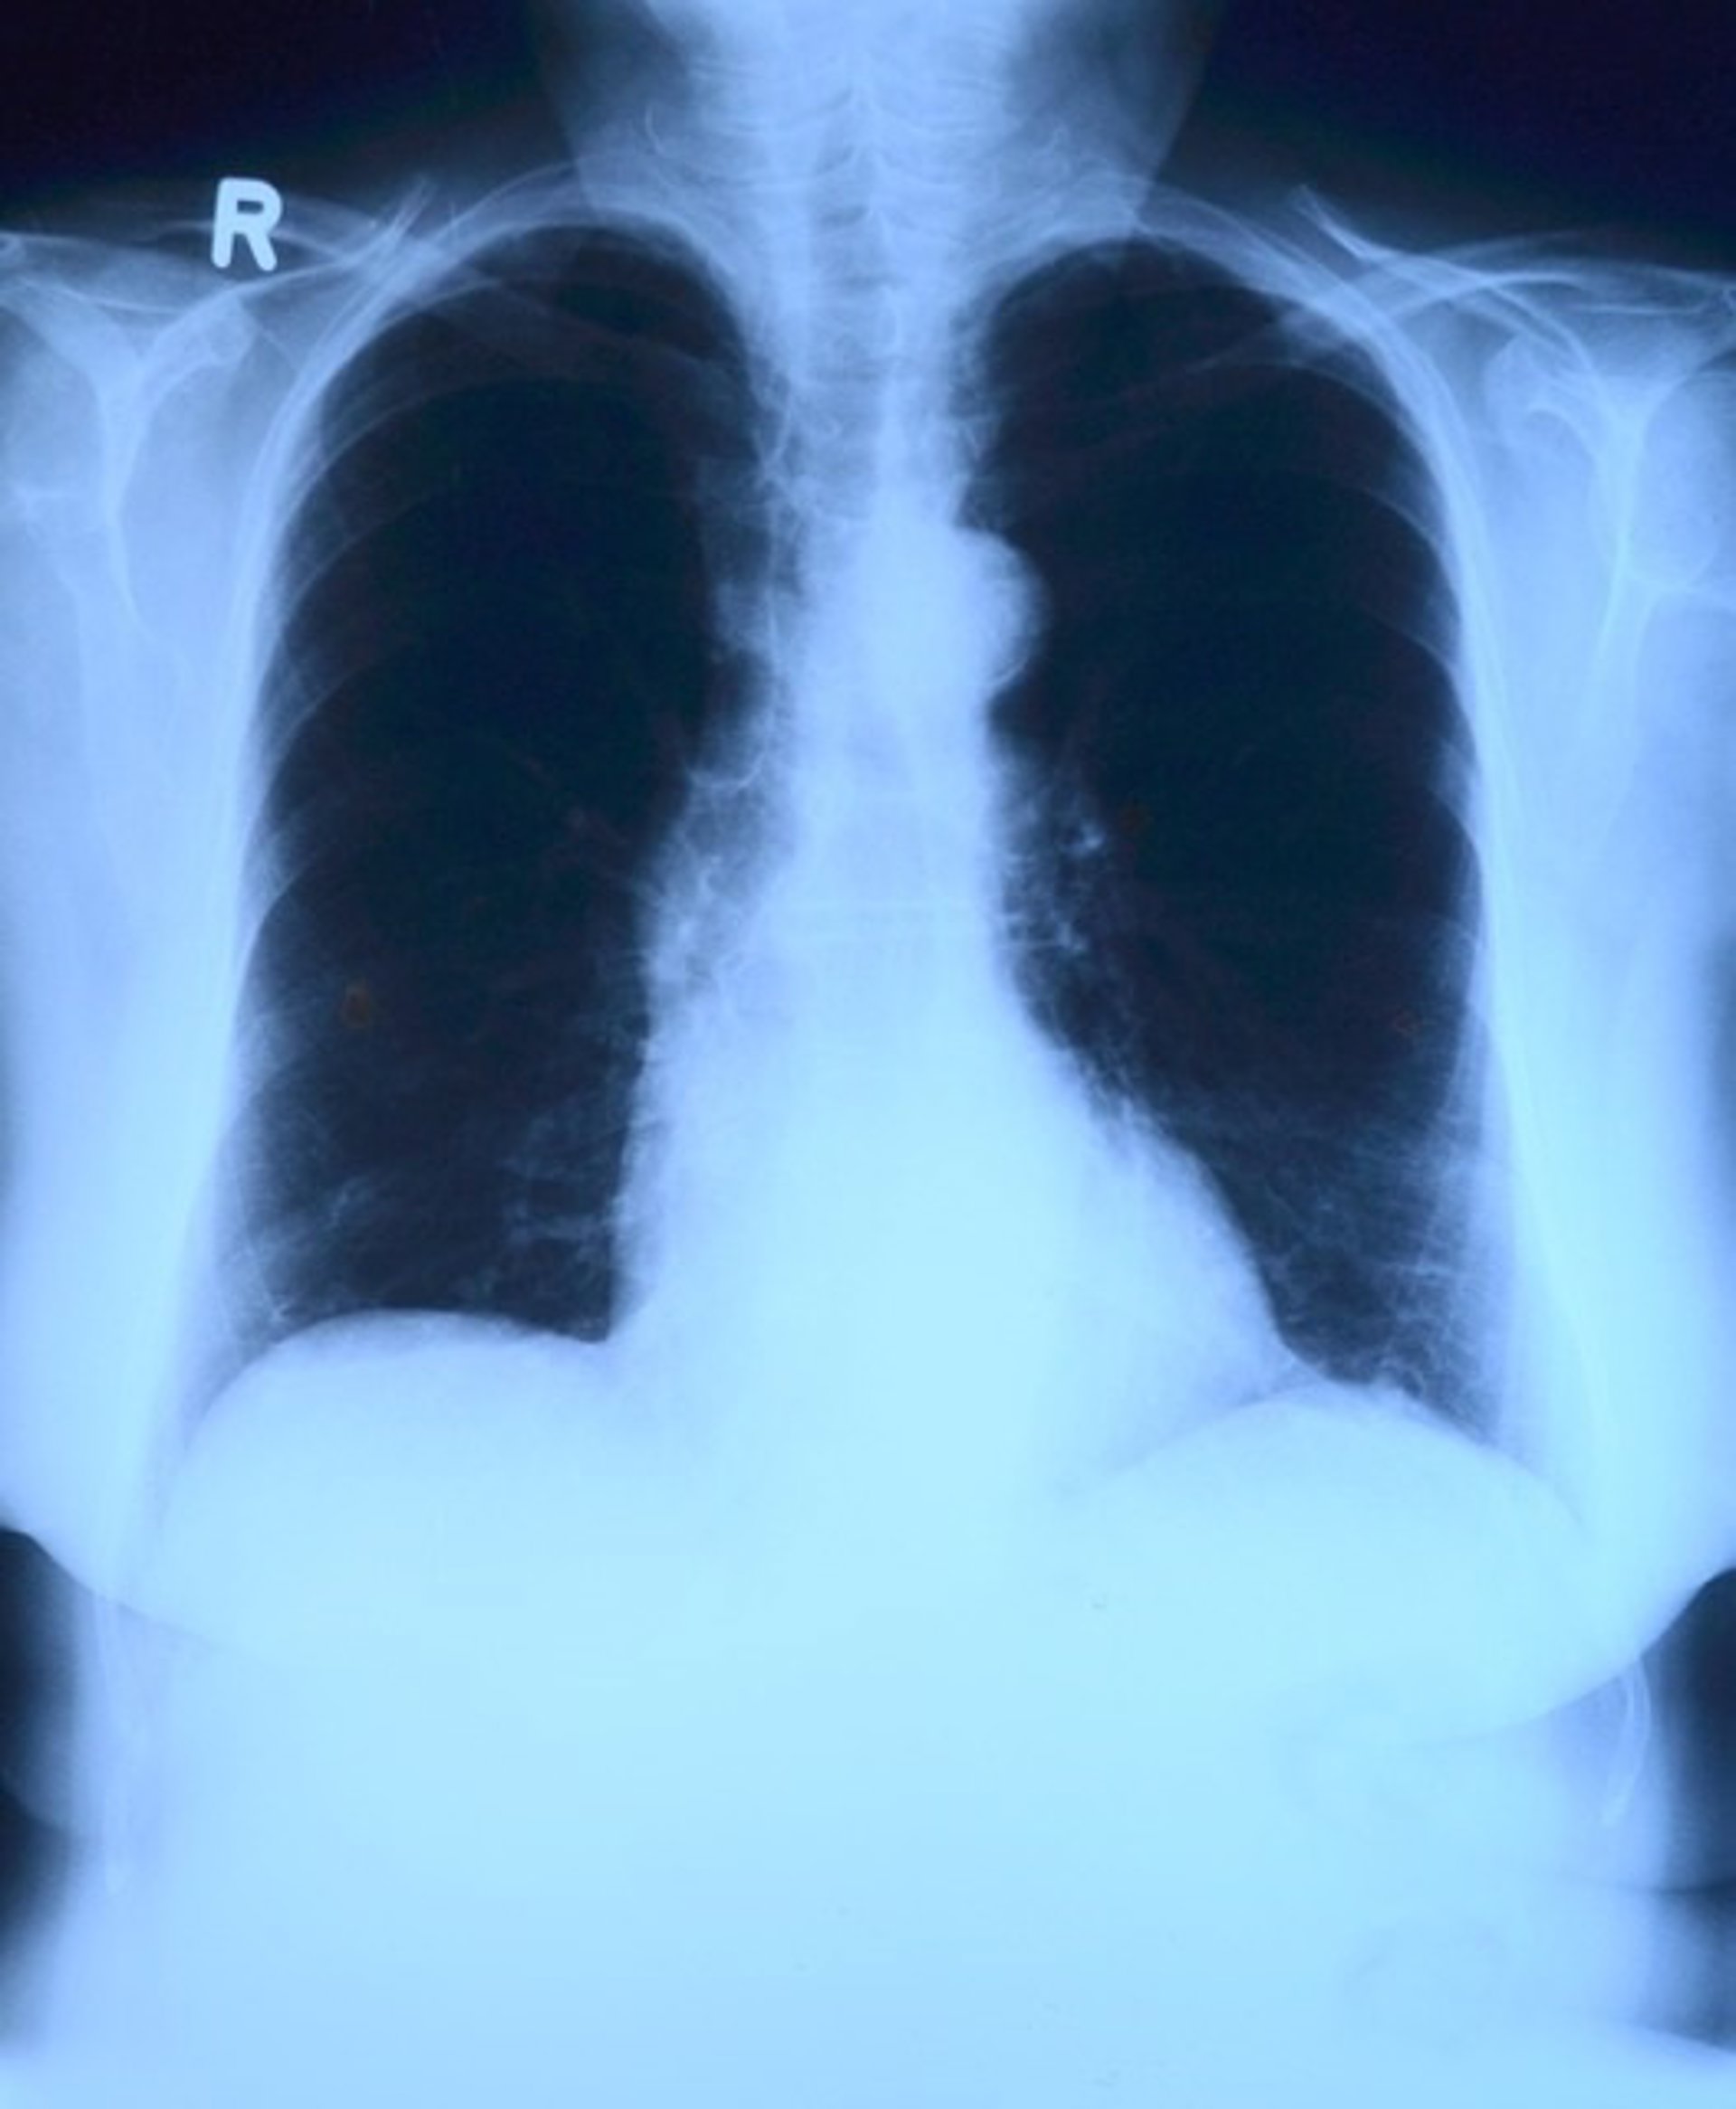

Disminuye la mortalidad por embolia pulmonar

Pulmones, radiografía

PIXABAY